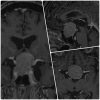

Los prolactinomas son tumores benignos de la hipófisis que producen cantidades excesivas de prolactina, una hormona fundamental en la regulación de la reproducción, el ciclo menstrual y la producción de leche. Aunque no son cancerosos, su impacto en la salud puede ser considerable, ya que alteran el equilibrio hormonal y, en algunos casos, ejercen presión sobre estructuras vecinas del cerebro, como los nervios ópticos.

Cuando el tratamiento médico falla o no es tolerado, la cirugía endoscópica endonasal se convierte en una excelente alternativa. Este procedimiento consiste en acceder al tumor a través de las fosas nasales utilizando un endoscopio de alta definición, lo que permite al neurocirujano llegar a la glándula hipófisis sin abrir el cráneo.